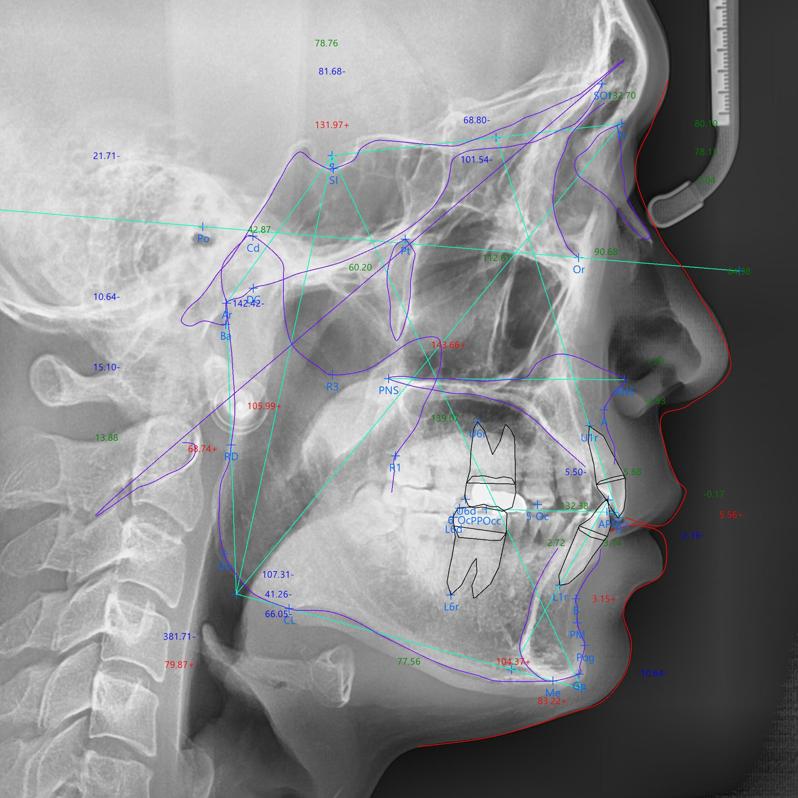

교정치료의 경우 위와 같이 엑스레이를 통해 많은 분석을 하고 그를 토대로 진행이 됩니다.

사진은 일례일 뿐이고 수많은 요소들을 분석해서 보기 때문에